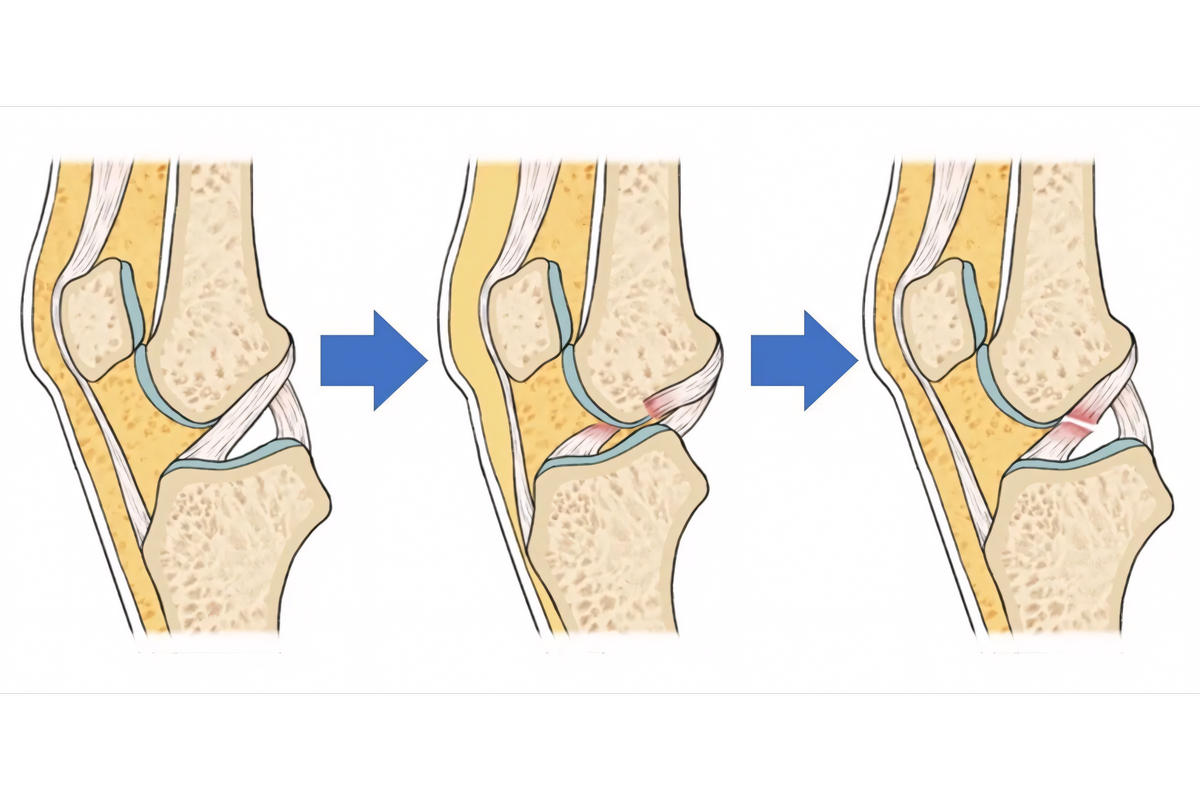

Η ρήξη ΠΧΣ συμβαίνει συχνότερα σε αθλήματα όπως ποδόσφαιρο, μπάσκετ και σκι. Στις περισσότερες περιπτώσεις πρόκειται για μη επαφής τραυματισμό.

Η βλαισότητα σε συνδυασμό με στροφική φόρτιση αποτελεί τον πιο συχνό μηχανισμό ρήξης πρόσθιου χιαστού.

Όταν προκληθεί ρήξη πρόσθιου χιαστού, το γόνατο χάνει τη φυσιολογική του σταθερότητα, δημιουργώντας αίσθημα αστάθειας και «φεύγει το γόνατο» κατά τη φόρτιση ή την άθληση.